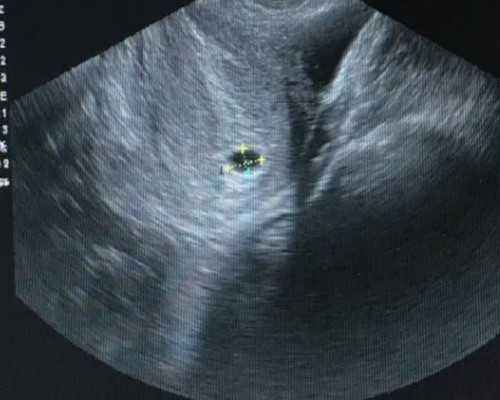

最近有一位来自甘肃张掖的姐妹说自己:18年检查出有子宫腺肌症,随后做了宫腹腔镜手术,然后医生说已经无自然受孕的可能,建议早点做试管婴儿,于是这里想问问子宫腺肌症做试管婴儿能有多大的成功率?